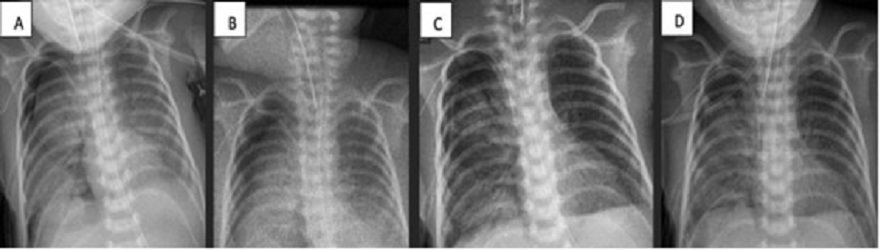

A 17-day-old male, born at 29 GW (1200 g), was diagnosed with NEC, respiratory distress syndrome, and pulmonary hypertension. (NEC required ex-laparotomy with Santully type ileostomy). Placed on CMV with FiO2 at 81% due to right tension pneumothorax. Air leakage persisted for 4 days along with increasing ventilatory parameters, that warranted ABPP (though the PAL criterion was not met fully). On day 23, ABPP was re-performed. No clinical improvement was seen. The patient developed hemodynamic instability requiring emergent thoracotomy. Multiple lesions were seen in the inferior lobe of the right lung. Primary closure was done without success, therefore fibrin patch (bovine serum purified albumin glutaraldehyde) was placed. Improvement was evident at 24 hours. The chest tube was removed on the 33rd day of life (Fig. 3).

Figure 3

A) Chest x-ray post 1st ABPP. B) Chest x-ray post 2nd ABPP. C) Chest x-ray post fibrin patch.